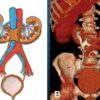

– Thận móng ngựa (Horseshoe Kidney) là do sự kết hợp cực dưới 2 thận ngang qua đường giữa bởi dải nhu mô hoặc dải mô xơ, sự kết hợp này thường ngang mức mào chậu và phía trước các cấu trúc mạch máu. Trục của thận hướng vào trong.

– Trong trường hợp điển hình thấy hình ảnh bóng 2 thận xoay trục với cực dưới hướng vào trong phía cột sống, gần nhau, cực trên xa nhau.

=> Case lâm sàng 1:

– Hai thận xoay trục, cực dưới hướng vào trong phía cột sống.

– Đài bể thận bình thường hướng lên trên ra ngoài => hướng xuống dưới.

– Phần nối hai cực dưới là nhu mô hoặc dải xơ vắt ngang phía trước cột sống.